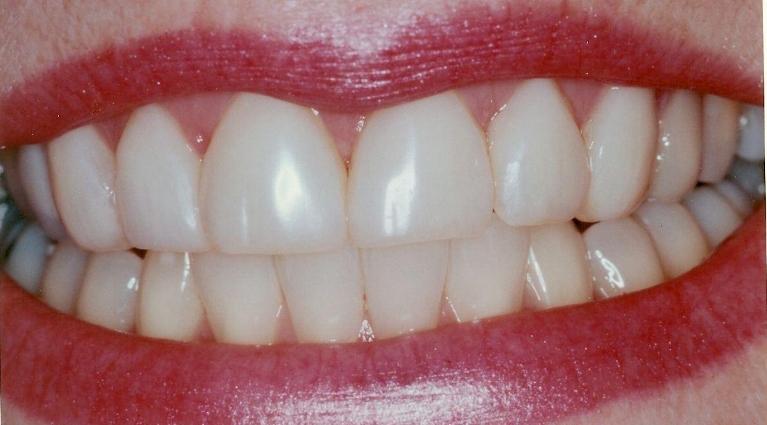

After

Repair of fractured incisor with composite resin.

This young Yale student fractured her two front teeth a few days after arriving in New Haven to begin her graduate school. She had recently bleached her lower teeth before leaving home.

Composite resin was bonded to the fractured area, and her treatment was completed within an hour.